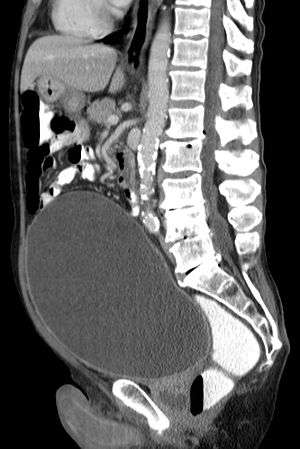

| Urinary retention with greatly enlarged bladder at CT. | |